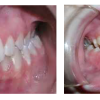

Agressiivne parodontiit

Seda parodontiidi vormi esineb umbes 1%-l elanikkonnast. On haiguse kiiresti progresseeruv vorm, mille puhul patsiendid kaotavad kõik hambad enne 30-35. eluaastat. Tavaliselt haigestutakse piimahammaste lõikumise ja puberteedi vahele jääval perioodil....